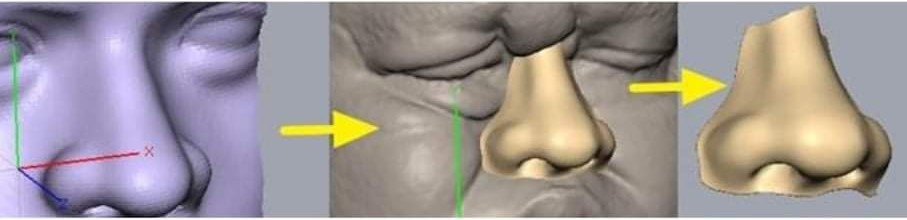

What is Asthi ?

Asthi is your one-stop solution for high-quality custom & Standard 3D-printed anatomical models for training, simulation and mock-up surgery. Our products are 3D Printed to provide medical professionals with a detailed and realistic representation of human bone, making it easier to study and understand complex medical concepts

Explore Asthi's Range of 3D Printed Anatomical Models.

Asthi offers four types of models to suit a variety of surgical applications. Our coloured models provide a detailed and vivid representation of anatomical structures, while our transparent models allow for greater visibility and depth perception. Our bone-like models offer a Realistic simulation of human bone. Whether you’re a surgeon, medical student, or researcher, Asthi’s 3D-printed anatomical models offer a comprehensive solution for surgical planning and training.

Asthi- Patient-specific 3D printed bone models

3D-printed bone models made of human bone-like material are accurate and highly detailed, providing a realistic representation of the patient’s bone structure. Our models are ideal for surgical training and planning, allowing medical professionals to practice and perfect their skills before performing surgeries on real patients. as they provide a realistic simulation of human bone. Making it easier for medical professionals to study and understand human anatomy”.